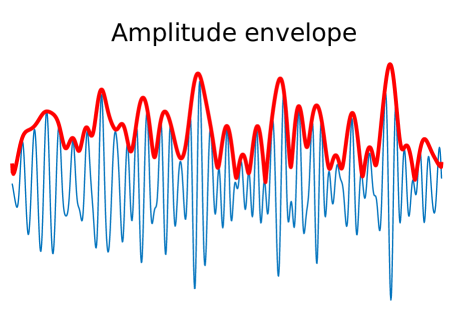

With the aim of studying the functional connectivity of the brain, for each subject, three 6 minutes resting state MEG scans have been performed, of which one session is used in our analysis. During the 6 minutes, data are collected from the sensors at 600K uniformly distributed time-points. Using FieldTrip, classical pre-processing is applied to the detected signals, such as low quality channels and low quality segments removal. Details of this procedure can be found in the HCP MEG Reference Manual. Moreover, we apply a band pass filter, limiting the spectrum of the signal to the Hz, also known as the beta waves. For the signal of each channel we compute its amplitude envelope (see Figure B.1) which describes the evolution of the signal amplitude. The measure of connectivity between channels that we adopt in this work is the covariance of the amplitude envelopes. Other connectivity metrics, such as phase-based metrics, have been proposed in the literature (see, e.g. Colclough et al., 2016, and references therein).

Here we present further material complementing the analysis in Section 6. In Figure B.1 we show the amplitude envelope computed from a filtered version of a signal detected by an MEG sensor. The covariance of the amplitude envelopes across different sensors is the measure of connectivity used in this work.